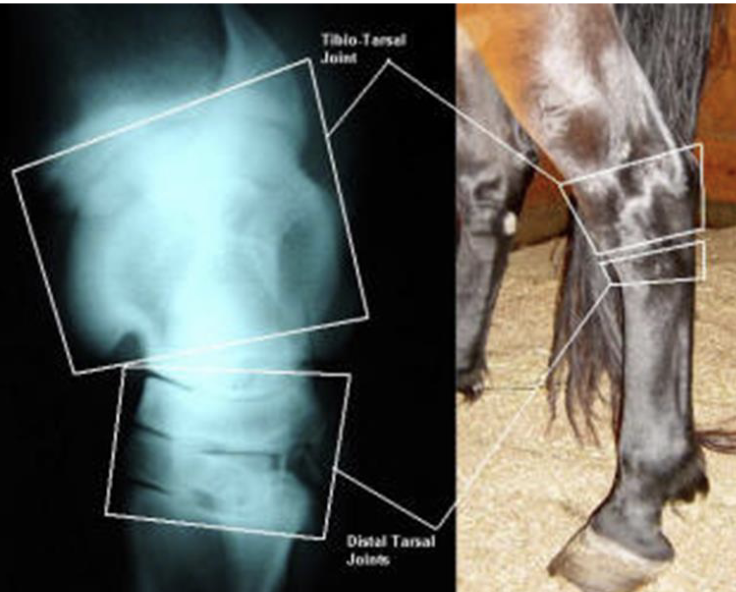

what are the bones of the tarsus

distal tibia, calcaneus + sustentaculum tali (fused), talus (+ medial and lateral trochlea), central tarsal bone, 3rd tarsal bone, 4th tarsal bone, fused 1 & 2 tarsal bone, proximal 2 3 and 4 metatarsal bones

joints of the tarsus

red- tibiotarsal (or tarsocrural)

green- proximal intertarsal

blue- distal intertarsal

purple- tarsometatarsal

which joints of the tarsus communicate w/ e/o

tibiotarsal and proximal intertarsal joints

which tarsal joints are the most common sites of arthritis in horses

distal intertarsal and tarsometatarsal

what is desensitized in a tarsometatarsal joint block

joint

what is desensitized in a distal intertarsal joint block

joint

what is desensitized in a tibiotarsal joint block (dont hit saphenous vein)

tibiotarsal joint & proximal intertarsal joint (communicate w/ e/o)